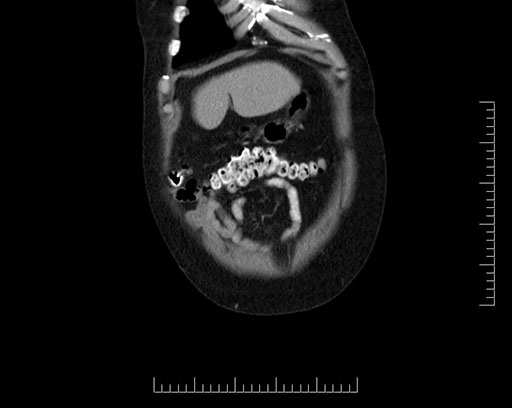

Imaging Analysis

Look through the patient's CT scan to identify any areas of concern for the necessary procedure.

Based on your CT findings, which issue(s) would give reason for "planned slowing down moment(s)" in this case?